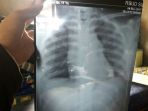

Siswi yang Tak Sengaja Telan Jarum Pentul akan Jalani Bedah Toraks di RSHS Bandung

Irma Sopiani (16), gadis yang tak sengaja menelan jarum pentul saat membetulkan kerudung, akan menjalani operasi atau bedah toraks

Keluarkan Jarum Pentul, Dokter di RSHS Pertimbangkan Bronkoskopi Lagi, Bedah Toraks Jalan Terakhir

Sebelumnya, Irma sudah mendapatkan prosedur medis bronkoskopi fleksibel melalui hidung namun tak berhasil.